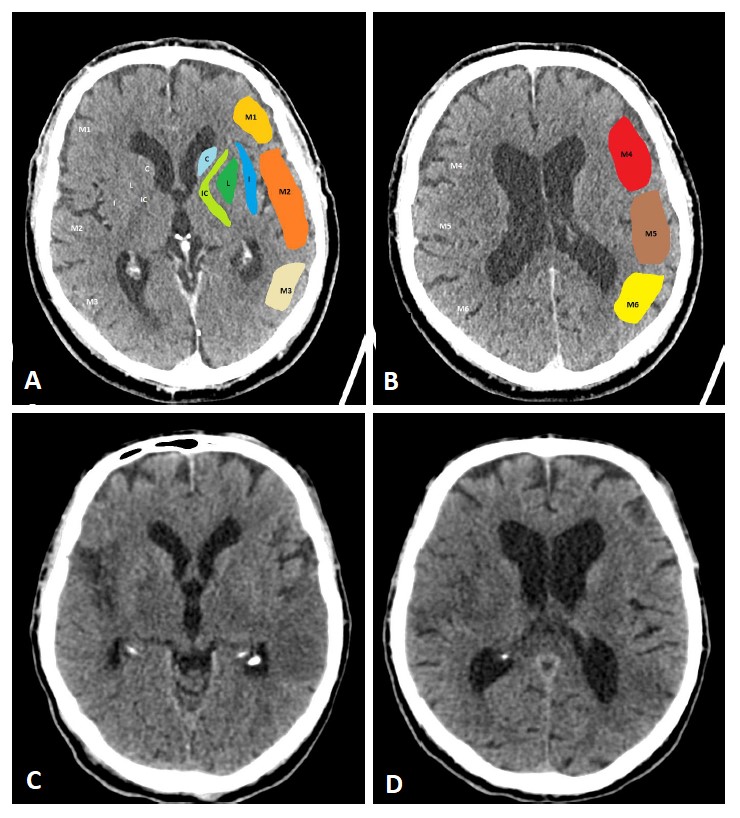

Fig. 1.ASPECTS. Visualization of the ASPECTS territories (A,B). The following areas are covered: M1 (anterior MCA cortex, frontal operculum), M2 (anterior temporal lobe, laterally to the insula), M3 (posterior temporal lobe, posterior MCA cortex), M4 (anterior MCA cortex superior to M1), M5 (lateral MCA cortex superior to M2), M6 (posterior MCA cortex superior to M3), insula (I), internal capsule (IC), caudate (C), and lentiforme nucleus (L). Each area accounts for 1 point. The maximum ASPECTS score is 10. Hypodensity in a described area leads to a deduction of one point. (C,D) show an example of CT ASPECTS. Hypodensity in the M2 and M6 areas is observed. Total ASPECTS: 8.